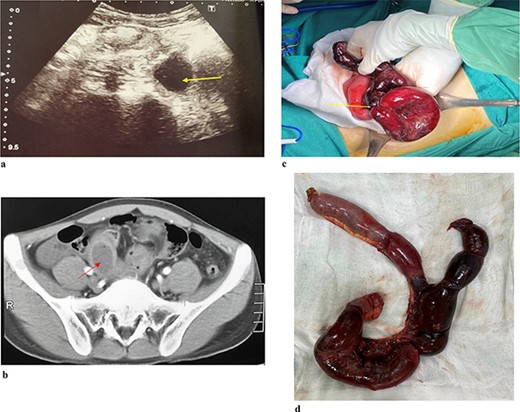

A 34-year-old female patient presented to the hospital due to a one-year history of right lower quadrant (RLQ) pain. There were no reported symptoms of weight loss or changes in bowel habits. She had no relevant medical or surgical history, and no family members had a history of gastrointestinal cancer. Physical examination revealed mild tenderness in the RLQ but was otherwise unremarkable. Abdominal ultrasound (Fig. 2) showed the right lumbar cystic lesion, adjacent to the ascending colon, the lesion appeared as a non-adhesive, anechoic structure with septations and no Doppler pattern. The size was ~35 × 17 × 26 mm. CT scan (Fig. 2b) demonstrated a cystic structure protruding into the lumen of the ascending colon, clearly margin, enhancing wall with a size was ~24 × 15 mm. A subsequent colonoscopy did not detect lesions. Based on the clinical and radiographic findings, she was diagnosed with a symptomatic colonic duplication cyst. Intraoperatively, an ascending paracolic cyst was found. The patient underwent laparoscopic right hemicolectomy, and she made an uneventful recovery and was discharged on the seventh day after the operation.

(a) Abdominal ulstrasound shows an arrow pointing to anechoic structure with septation. (b) Axial CT scan showing an arrow pointing to a cystic structure protruding into the lumen of ascending colon. (c) Arrow pointing to colonic duplication cyst. (d) Microscopic examination, the inner lining of the cyst consisted of flat epithelium containing mucin.

The macroscopic examination of the histopathology sample (Fig. 2c) identified a 20 mm cystic mass located adjacent to the ascending colon. Upon microscopic examination (Fig. 2d), it was observed that the inner lining of the cyst consisted of flat epithelium containing mucin.